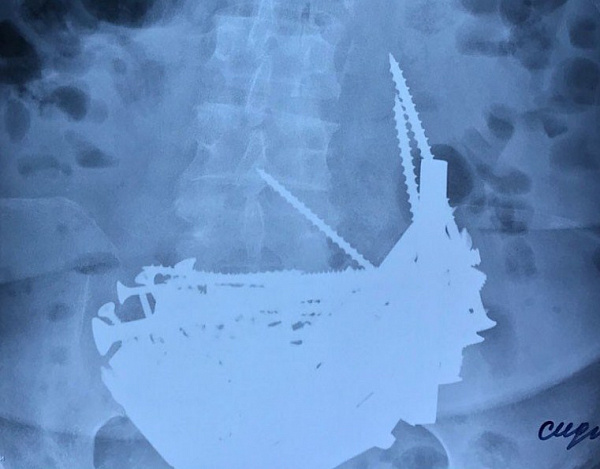

Врач отделения гнойной хирургии Булат Шоболов и хирург торакального отделения Чингис Батуев назначили рентген брюшной полости, позже на рентгенограмме они увидели громадный инородный объект в желудке.

- Детальное изучение снимка вызвало опасение угрозы перфорации стен желудка, то есть возможное возникновение сквозных отверстий в желудке, сопровождающееся попаданием его содержимого в свободную брюшную полость. Пища, попавшая в брюшную полость, на третьей стадии вызывает гнойные процессы в организме. Требуется немедленное оказание медицинское помощи пациенты во избежание летального исхода, - пояснили в РБК им. Семашко.

В срочном порядке пациентке под общим наркозом были сделаны лапаратомия и гастротомия. Лапаратомия - операция на брюшной полости, когда все манипуляции проводятся через один разрез на передней стенке живота. Гастротомия - операция, которая заключается во вскрытии полости желудка через переднюю брюшную стенку.

Врачи добрались до желудка и очень сильно удивились, когда начали удалять инородные тела. Длинные гвозди, крупные шурупы, болты, гайки, дверные шпингалеты, отрезки арматуры длиной до 15 см и даже серебряная цепочка 925 пробы. В итоге из желудка было извлечено 152 железных предмета, которые уже начали окисляться, то есть сколько они там находились никому не известно, кроме самой женщины.

Когда все гвозди и шурупы были удалены, выяснилось, что стенки желудка в полном порядке, перфорация отсутствует и угроз для жизни и здоровья пациентки больше нет.

В конце операции был сделан контрольный рентгеновский снимок для 100% подтверждения удаления всех инородных тел. Затем, по завершении, желудок и брюшную стенку зашили. На желудок наложили два ряда швов. Наличие рубца на стенке желудка после гастротомии не вызывает каких-либо осложнений.